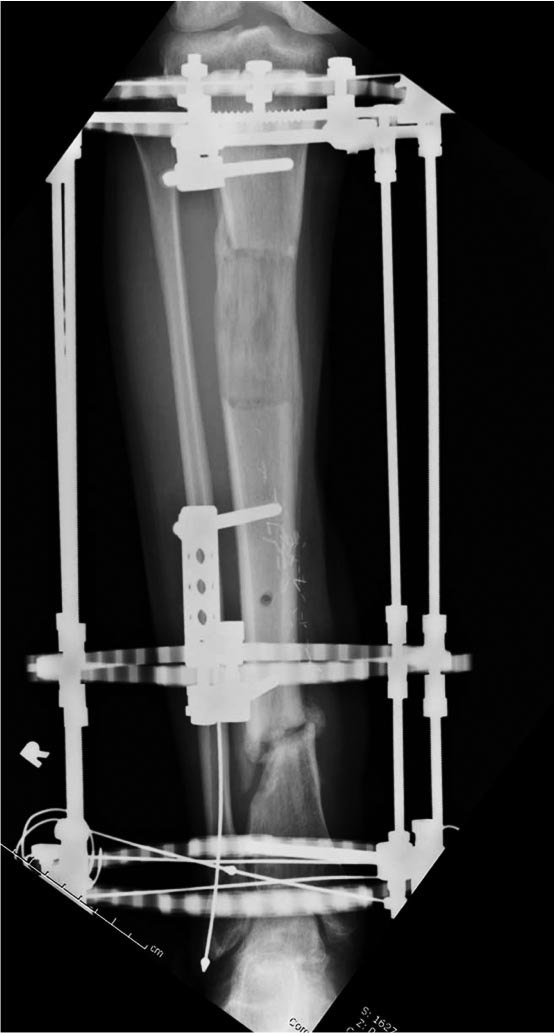

Данный случай не огнестрельная рана, а результат мотоциклетной аварии. Независимо от повреждения при таких обширных дефектах мягких и костной тканей применяется схожая тактика. Как видно, после нескольких I&D для создания “pseudo membrane” применили цилиндрический блок из цемента. Дефект мягких тканей закрыли свободным Anterior Thigh Graft. Из малого доступа цилиндр удален небольшими кусочками, а пространство заполнили бусами для освобождения пространства. По мере приближения регенерата освободили пространство удалением бус через небольшой разрез. Этап созревание регенерата можно было ускорить усилением интрамедуллярным гвоздем, но решили закончить методом Илизарова.

Теперь по поводу данного случая - “спейсер” из цемента предупреждает инфекцию и сохраняет пространство. Но вместо “бус” “цилиндрическая форма” более удобная, вокруг нее образуется ровная трубчатая поверхность “псевдо-мембраны” что в дальнейшей позволит закрыть небольшие дефекты “графтом” или во время удлинения облегчает скольжение регенерата как по трубке.